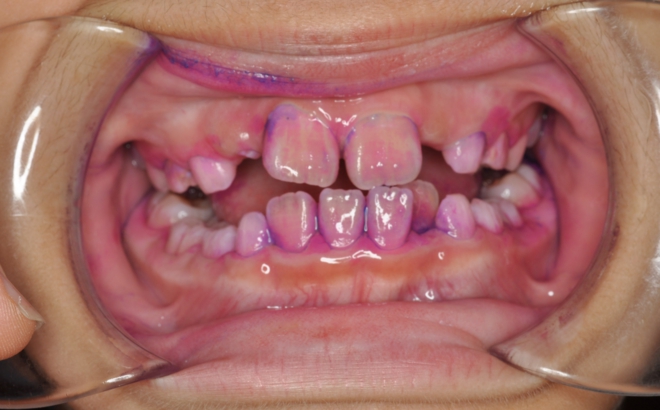

不正咬合のある人は歯ブラシがしにくく、まして矯正装置を付けるとむし歯や歯周病のリスクが大きくなります。そこで当院では矯正治療中の患者さん全てにツートーン(病原性の強いプラークが青く、そうでないプラークは赤く染まる染め出し液)での染め出しとブラッシング指導、PTC(プロフェッショナルトゥースクリーニング)を行っています。